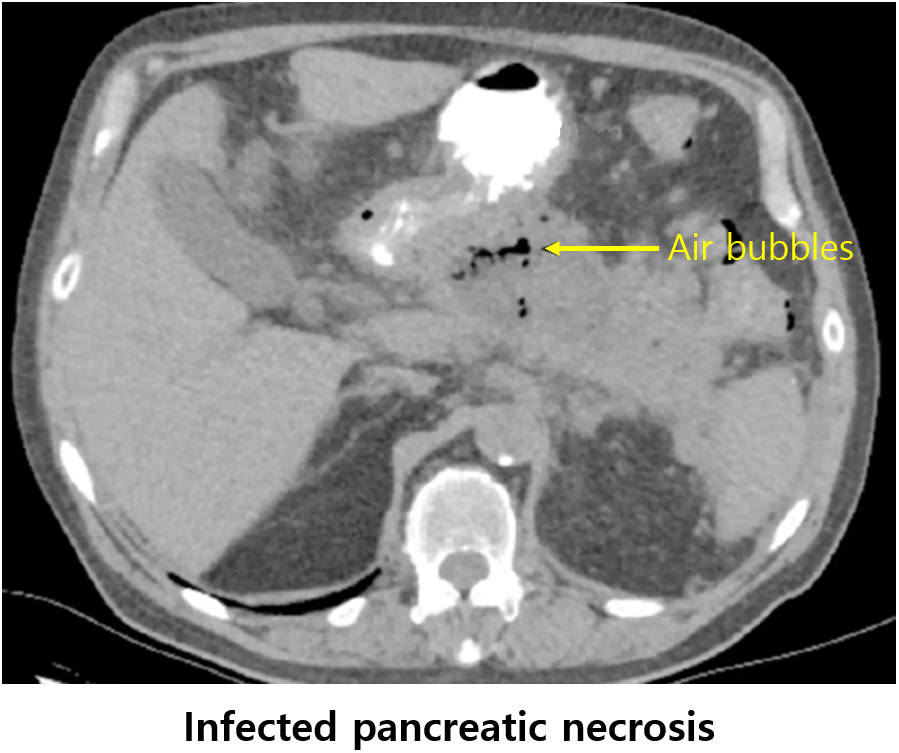

3) 감염성 췌장괴사(infected pancreatic necrosis)

(1) 정의: 괴사성 췌장염에 감염이 동반된 상태

영상검사: CT/MRI - 괴사 조직 내 공기방울이 관찰될 수 있음

감염성 췌장괴사

• CT: 괴사성 췌장염의 fluid collection 내부의 air bubbles

• 치료: 항생제 + (배액술 or 괴사조직제거술)